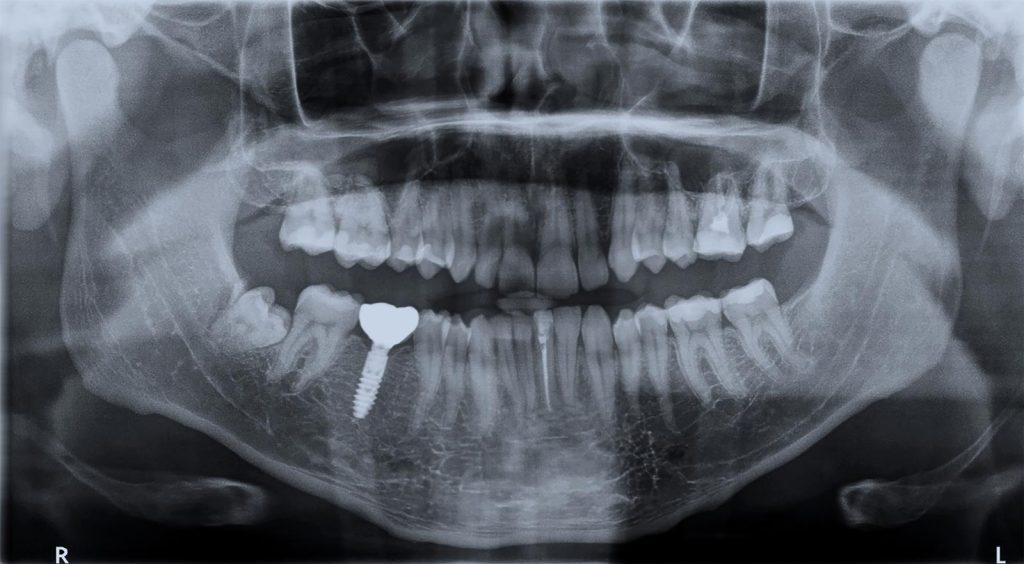

Valutazione preliminare e pianificazione

La prima fase è la visita specialistica, durante la quale il professionista raccoglie informazioni sullo stato di salute generale del paziente, esamina il cavo orale ed esegue esami diagnostici come radiografie o TAC dentali. Questa fase è fondamentale per valutare la quantità e la qualità dell’osso disponibile e per pianificare l’intervento in modo sicuro e personalizzato.